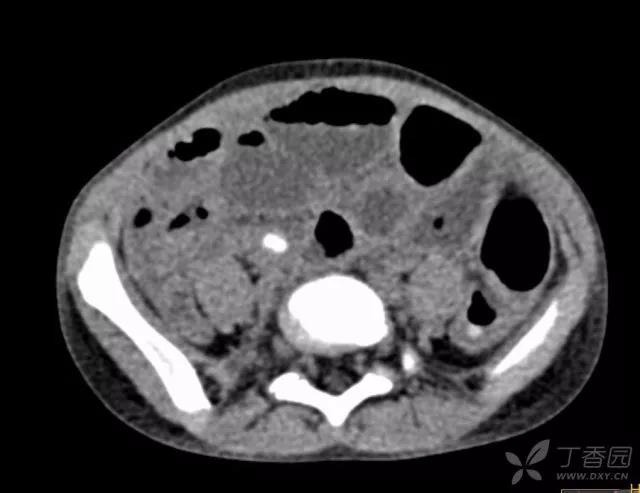

4岁,女童,3 天前开始腹痛,2 天前就诊当地医院,治疗后腹痛不缓解,X 片是小肠梗阻,建议至上级医院就诊。

至本院就诊时:精神萎靡,腹部拒按,经检查考虑急性阑尾炎穿孔并腹膜炎,予急诊手术。

下图为术中所见:

术中见可以看到:无大网膜包裹的阑尾,肿胀、化脓,中段穿孔。罪魁祸首是阑尾炎!

城门失火殃及池鱼,阑尾与右侧附件紧挨在一起,都是肿胀、敷脓苔!

小小的腹腔,胀胀的肠管,几乎没有操作空间,开腹手术似乎是最佳选择,要想冲洗腹腔干净,没有 6 cm 切口,几乎是不可能的。